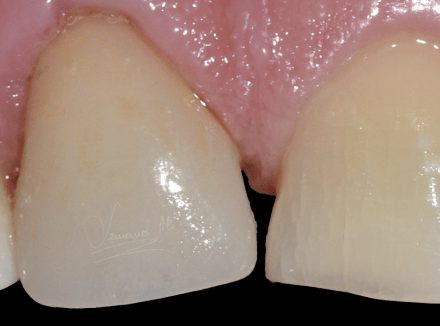

Установка керамических виниров

Пациент, возвращаясь вечером с работы, поскользнулся и упал на льду. Разбил губу с передними зубами. При травме нерв был повреждён и начал портиться, в результате чего эмаль зуба начала темнеть. Без применения виниров или коронок в такой ситуации цвет уже не восстановить. Было принято решением восстановить зубы при помощи керамических виниров.